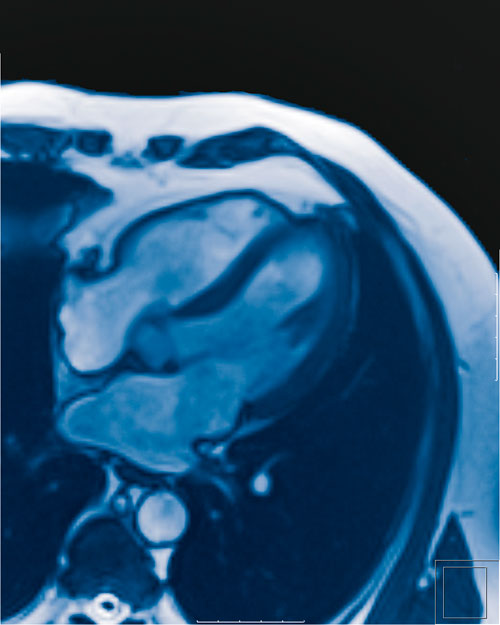

Kernspintomographie des Herzens

Die Kernspintomographie des Herzens stellt eine hervorragende ergänzende Methode ohne Strahlenbelastung dar, um sowohl die Funktion als auch die Morphologie des Herzens zu beurteilen. Die Untersuchung wird in unserem offenen Hochfeld-Kernspintomographen (Feldstärke 1,5 Tesla) durchgeführt. Es wird ein Kontrastmittel intravenös appliziert. Hierduch können die anatomischen Strukturen des Herzens einschließlich Bewegungsanalyse, Narben und Entzündungen exakt dargestellt werden.

Um die Funktion des Herzens genauer zu beurteilen, kann eine zusätzliche Belastungsuntersuchung durchgeführt werden. Hierbei wird durch ein spezielles Medikament (Adenosin) der Herzschlag beschleunigt. So können auch Minderdurchblutungen oder andere Erkrankungen des Herzens diagnostiziert werden, welche sich in Ruhe nicht zeigen. Sollte im Rahmen einer CT-Koronarangiographie eine mittel- bis höhergradige Verengung (Stenose) an einem Ihrer Koronargefäße gefunden werden, so gibt die Kernspintomographie des Herzens Aufschluss über die Sinnhaftigkeit einer möglichen Intervention (Ballondilatation oder Stentimplantation). Diese ist nämlich nur dann sinnvoll, wenn hinter der Gefäßverengung eine Minderdurchblutung nachgewiesen wird.